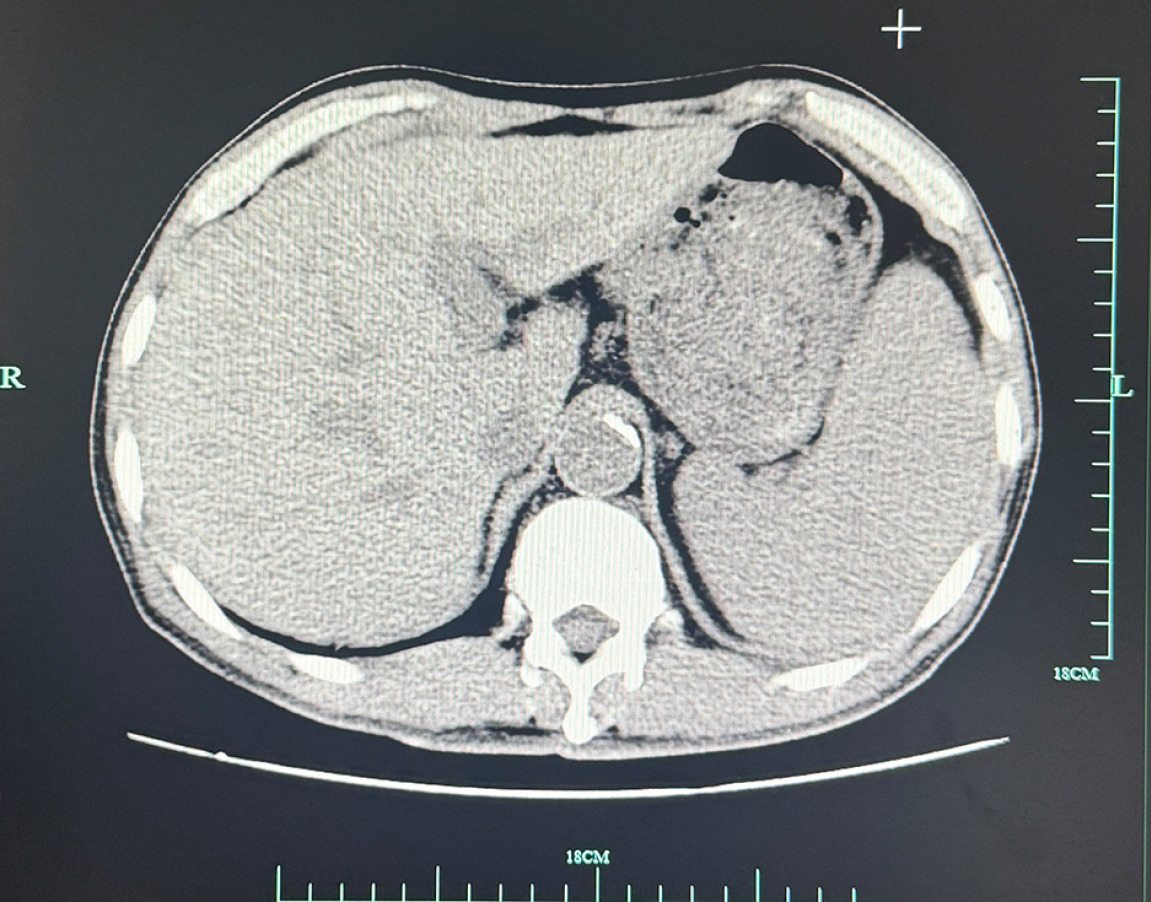

An upper-abdominal CT scan performed on March 22, 2022, demonstrated findings consistent with cholecystitis and multiple gallstones. In addition, a potential communication was noted between the gallbladder fundus and the gastric antrum. Several gallstones were identified in the gastric antrum, along with mild periantral fluid accumulation and multiple small regional lymph nodes. A small volume of perihepatic fluid was also detected (Figure 1).

Figure 1

Figure 1 This computed tomography image is the abdominal cross-sectional image of this patient on March 22, 2022. In the image, an oval high-density gallstone (about 5.0 cm in diameter) was embedded in the proximal duodenum, resulting in significant expansion of the stomach. Edema of duodenal wall and local intestinal lumen stenosis can be seen around the stone. In addition, the gas shadow in the gallbladder suggests that there may be abnormal channels between the gallbladder floor and the gastric antrum, with a little exudation around the gastric antrum.